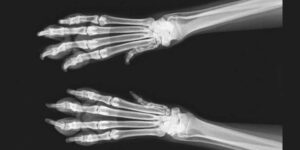

Digital imaging can help better communicate health issues and treatment plans to pet owners. And when it comes to patients getting the care they need, shouldn't you use every tool at your disposal?